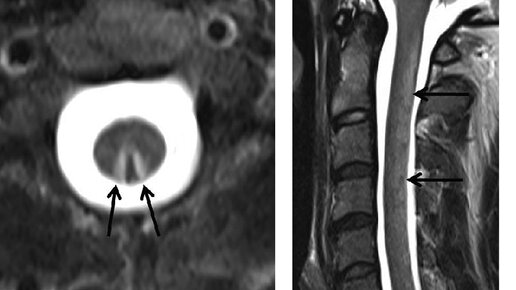

Когда появляются и нарастают онемение и неприятные ощущения в ногах, нарушается походка , первые мысли у невролога возникают о полиневропатии ( которой посвящена предыдущая статья ). Но что если Слабость в обеих ногах может означать наличие опухоли, воспаления или нарушение кровоснабжения в определённых участках головного и спинного мозга. Поэтому назначается высокоточные (и дорогостоящие, к сожалению) После этих исследований, картина, конечно, может проясниться. Но не всегда...